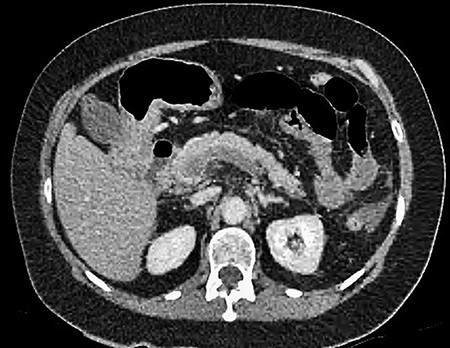

A 61-year-old female presented to a regional hospital with a 3-week history of intermittent diarrhoea, vomiting and generalized abdominal pain. She had a diffusely tender abdomen but was not peritonitic, and was shocked with a heart rate of 110 beats per minute, blood pressure of 89/45 mmHg and was peripherally cool. Her blood tests revealed a lactate of 7.2 mmol/L, which worsened to 7.8 mmol/L during resuscitation with intravenous fluids, and white cell count was 30.9 × 109/L, with an international normalized ratio (INR) of 1.4. She had an acute kidney injury with a creatinine of 119μmol/L and estimated glomerular filtration rate (eGFR) of 43 mL/min/1.73m2. Computed tomography (CT) revealed extensive thickened loops of non-enhancing small bowel with pneumatosis, moderate free fluid and a large splenic infarction. There was extensive thrombosis of the splenic vein and superior mesenteric vein extending into the portal vein to the level of the porta hepatis. Her background history included factor V Leiden and protein S deficiency, for which she had been non-compliant with warfarin during this illness. She had no surgical history (Figs. 1–5).

CT showing multiple thick-walled, non-enhancing loops of small bowel.

CT showing complete occlusion of the portal vein at the level of the porta hepatis.

CT showing an area of splenic infarction due to venous ischaemia.